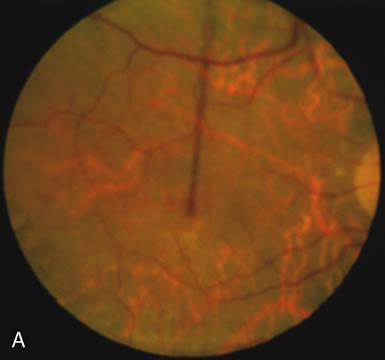

The carrier female with XLR RP, who has the golden tapetal sheen reflex, has normal FA findings. This suggests that the abnormal reflex is not due an abnormal pigment layer or deposition7 (Fig. 2A and B).

In Oguchi's disease the hallmark fundus finding is a yellow metallic sheen (Fig. 2C). A similar sheen has been seen in progressive cone dystrophies and juvenile macular degeneration.7 In all these diseases the abnormal reflex does not affect the normal transmission of fluorescein dye (Fig. 2D). The normal FA suggests that, like findings in the carrier female in XLR RP, the abnormal retinal reflex in this disease is unrelated to pigment concentration or distribution.